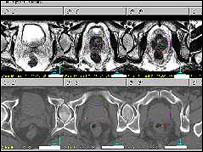

Imagem da próstata